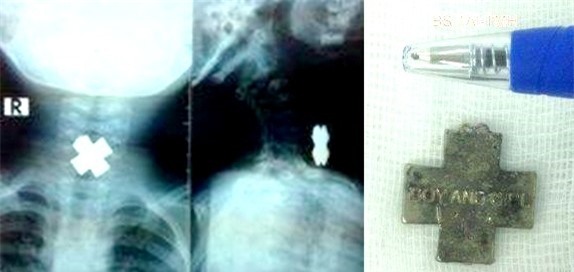

Kết quả X-quang cho thấy dị vật mắc trong cổ bé rất to, hình chữ thập nằm chiếm hết lòng thực quản. Các bác sĩ nhận định khả năng dị vật gây trầy, rách thực quản rất cao.

Mặt dây chuyền hình chữ thập chắn ngang thực quản bệnh nhi. Ảnh: BV Nhi Đồng. |

Đội ngũ y tế quyết định tiến hành gây mê, dùng thủ thuật gắp dị vật ra khỏi thực quản cho bệnh nhi. Kết quả kiểm tra cuối cho thấy lòng thực quản của bé An chỉ tổn thương nhẹ niêm mạc, có thể nhanh chóng bình phục.